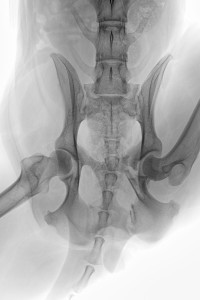

Auf der RÖ-Aufnahme vom 06. Jan. 2016 ist eine deutliche Kallusbildung an allen Frakturstellen zu erkennen. Wir machten uns allerdings Sorgen, dass es zu einer überschießenden Kallusreaktion am caudalen Bereich des Acetabulums kommen könnte, die dann die Bewegung des Femurkopfes einschränken könnte. Ab Januar wurde die Physiotherapie / Unterwasserlaufband dann zwei Mal wöchentlich durchgeführt und zu Hause mit isometrischen Übungen (wie Trampolin-Wippen, auf 3 Beinen stehen, Podesttraining usw.) begonnen, um die immer noch schwachen Oberschenkelmuskeln zu trainieren. Gleichzeitig haben wir das Ergodyn Gerät jeden zweiten Tag eingesetzt, mit längerer Anlegezeit (ca. 15-20 Min.).